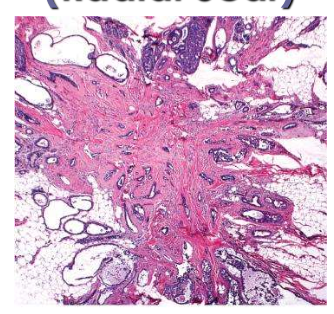

phyllodes tumor histo

circumscribed but not encapsulated

interlacing celfts

necrosis and hemorrhage due to rapid growth

leaf-like or epithelium lines clefts or cysts

incresaed stromal cellularity with overgrowth